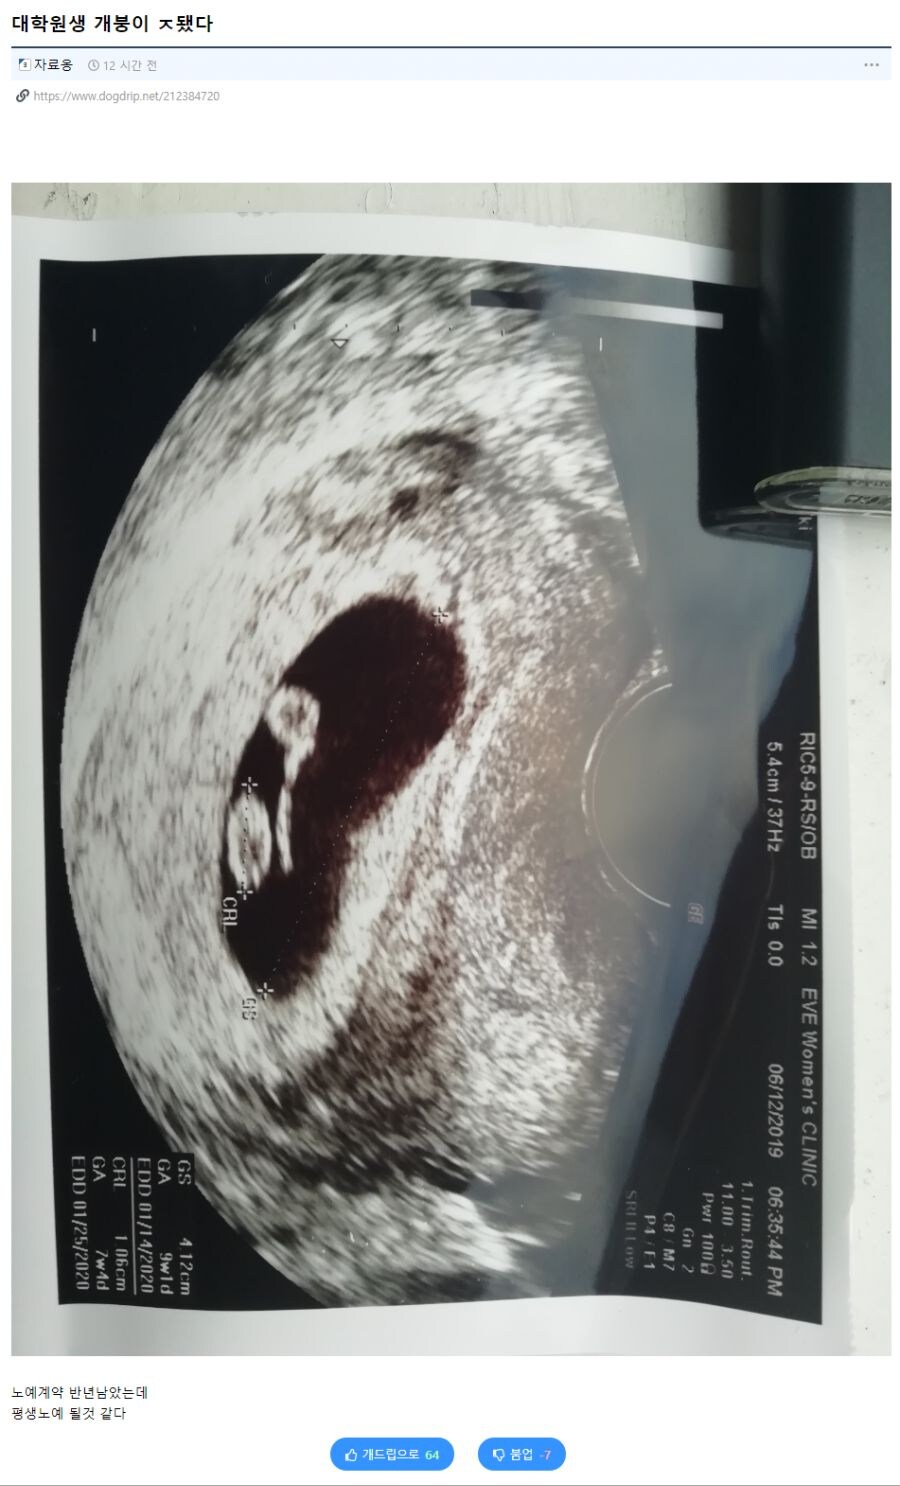

평생 노예 계약을 찍어버린 대학원생.jpg Anonymous | 2025.11.08 14:20 | 조회 7 https://qquing.net/bbs/board.php?bo_table=humor&wr_id=1696104 주소 복사 이전글 다음글 랜덤 만화 목록 본문 추천 0 비추천 0